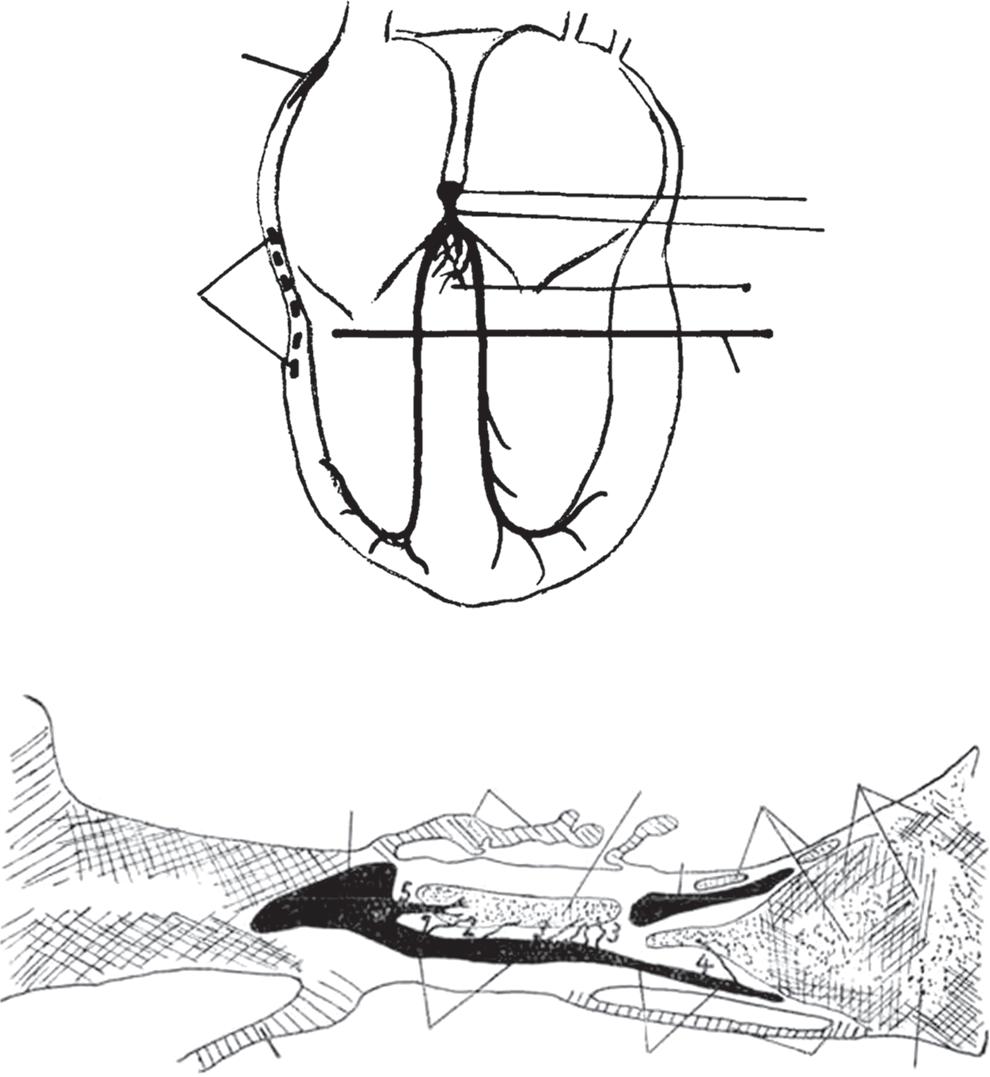

Figure 6: Ventricular Ablation Lesion Assessment

Preprocedural LGE-MRI (1 day before VT ablation)

Ablation points

Post-ablation LGE-MRI (3 months after VT ablation)

Left: 3D reconstruction of the left ventricle with LGE-based colour-coding based on thresholds for dense scar (red, >60% maximum of signal intensity) and border zone (yellow, 40–60% of maximum signal intensity), mapped using ADAS 3D. Shown are the layers at 30% of the transmurality (from endocardial to epicardial). For the post-ablation LGE-MRI (lower panel), an additional 3D reconstruction of the manually defined dark core in red (black arrow) is depicted. Blue lines indicate the plane of the short-axis slices on the right. The ablation points (TactiCath, Abbott Medical) are visualised using a 3D mapping system (EnSite Precision, Abbott Medical). Middle: Overlay of the T1-weighted short-axis slices with the colour-coding described above. The central hypoenhancement dark core of the ablation lesion is manually delineated (red border) to avoid misinterpretation as healthy tissue. Right: T1-weighted short-axis LGE-MRI slices without colour-coding. LGE = late gadolinium enhancement; VT = ventricular tachycardia.